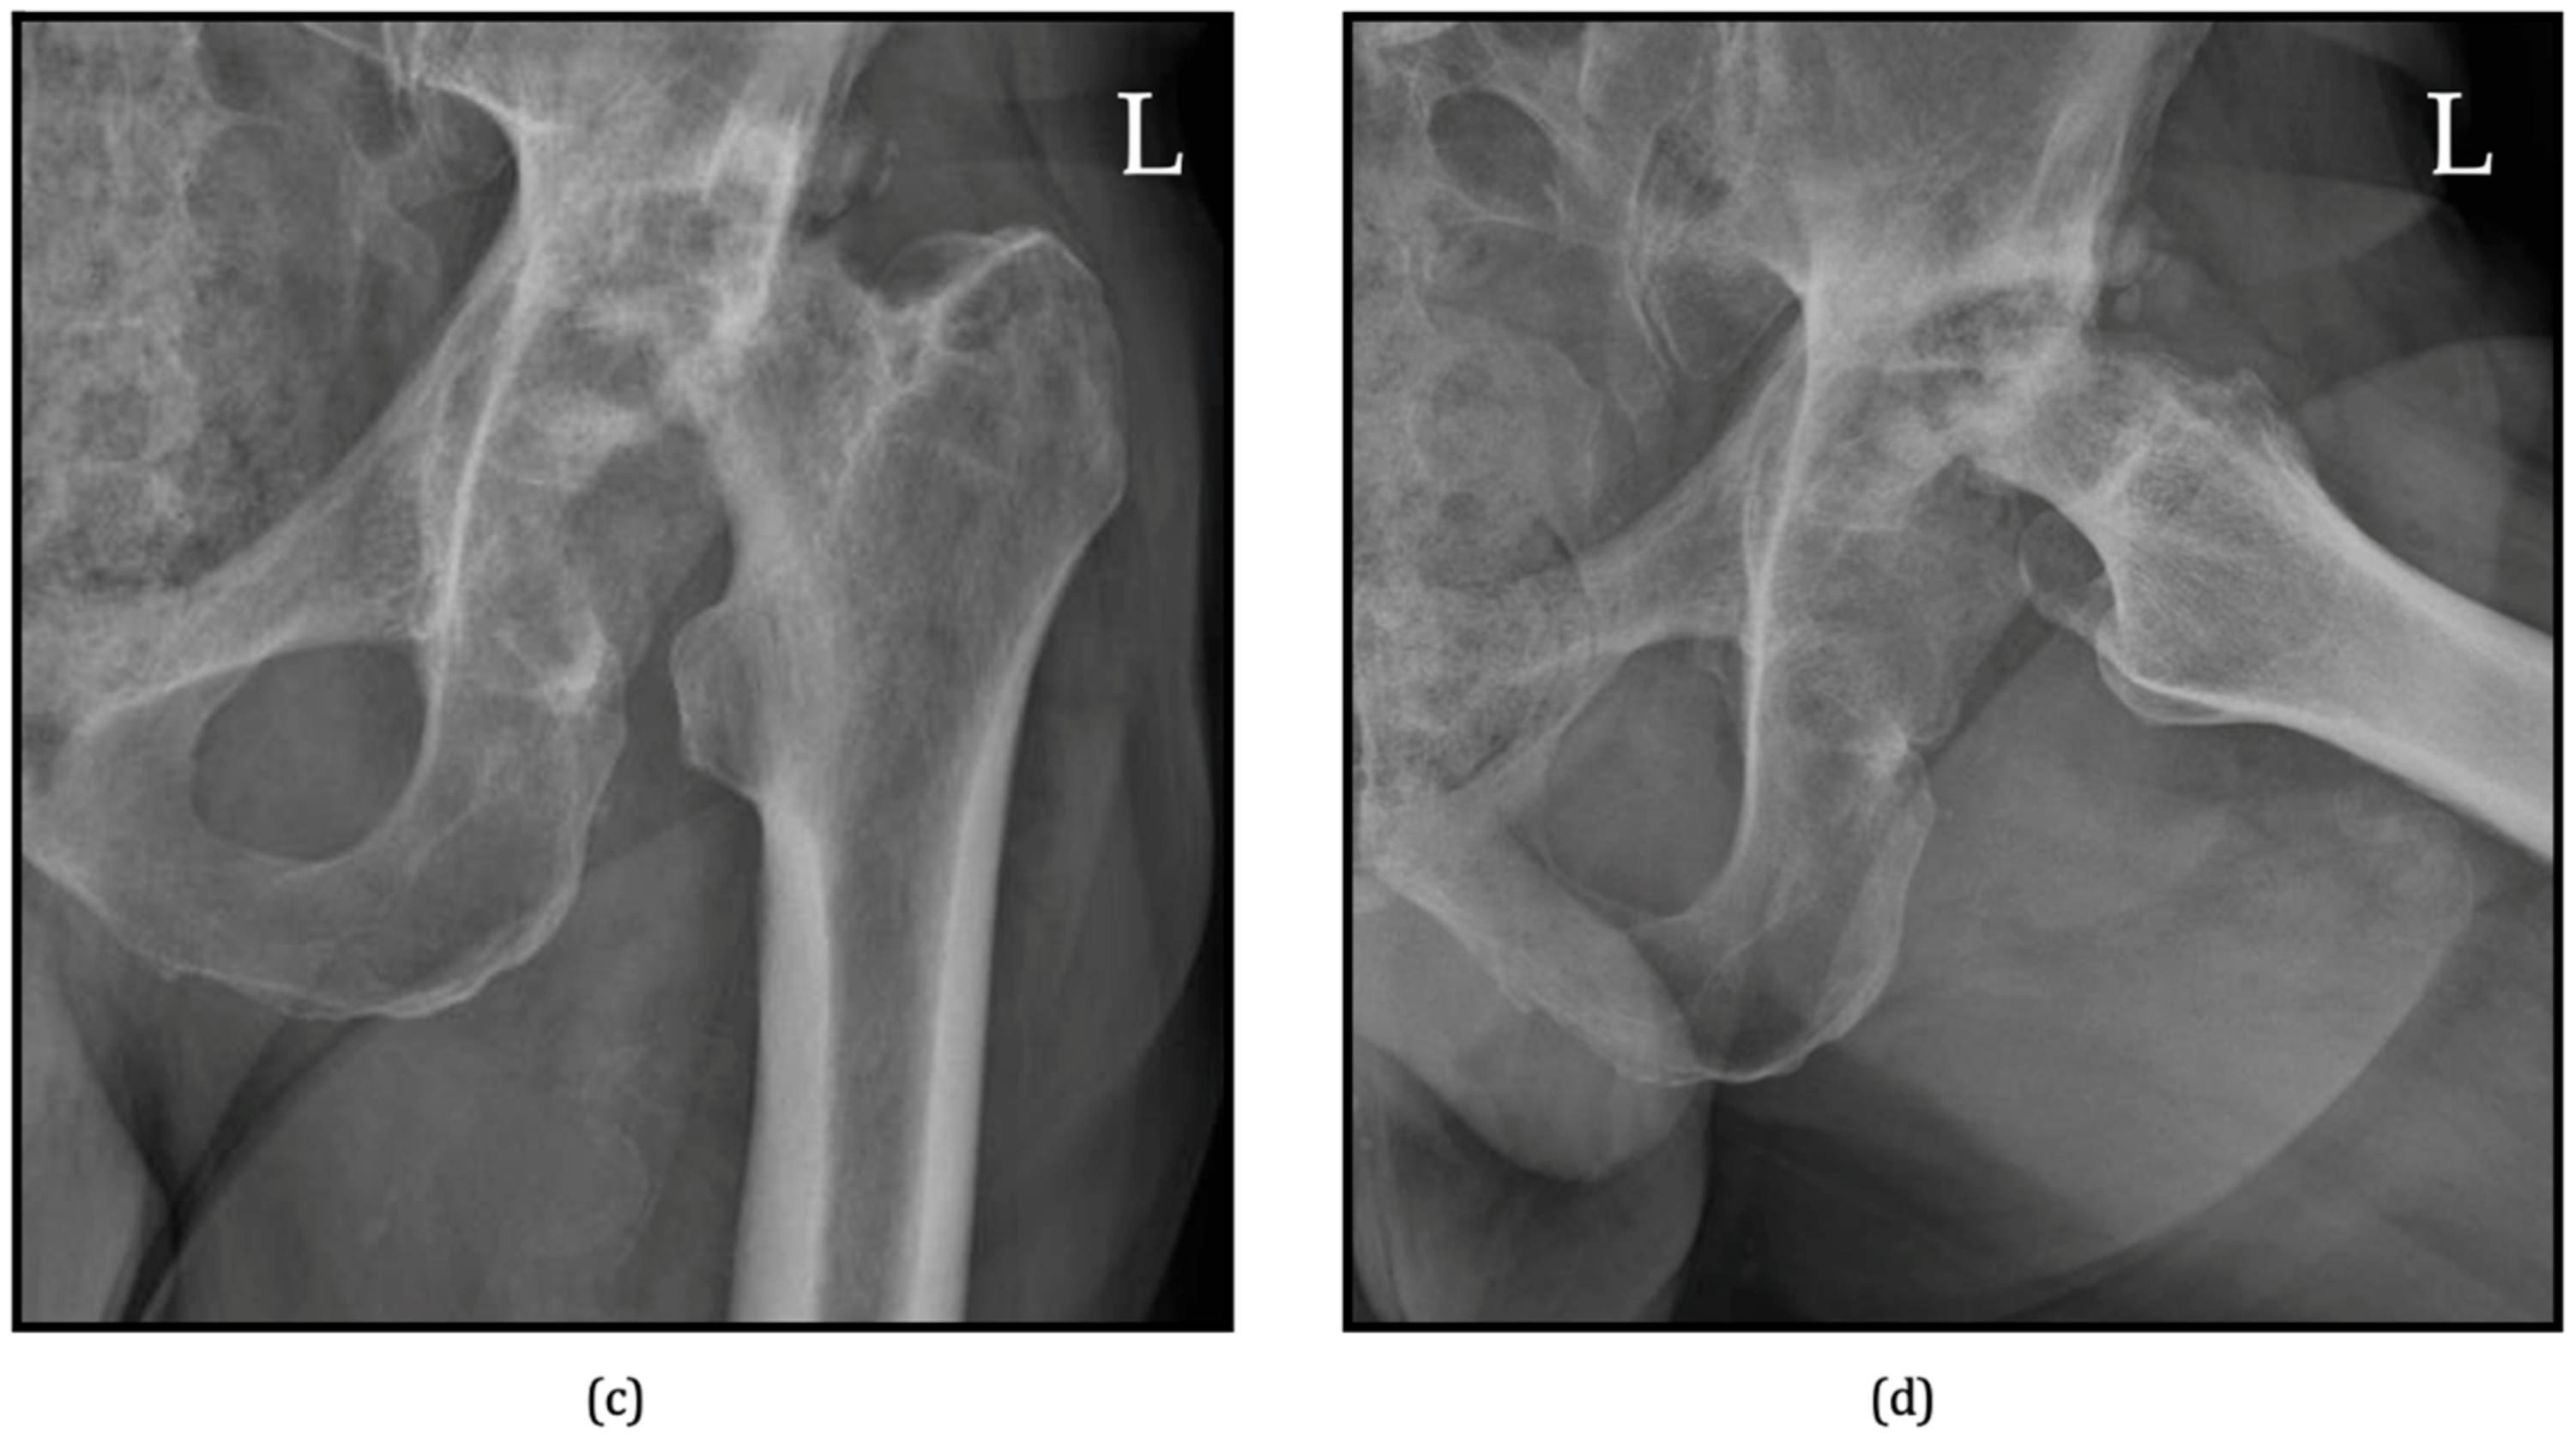

6.1. Radiographs

| Zazgyva A, Pop TS et al. [71] | 2017 | Grade I | Partial joint space narrowing; no deformation/ascension of the femoral head. |

| Grade II | Complete disappearance of the joint space; deformed femoral head and acetabulum; femoral head ascension ≤ 0.5 cm above radiologic teardrop. | ||

| Grade III | Complete disappearance of the joint space; partial osteolysis of the femoral head; femoral head ascension > 0.5 cm above radiologic teardrop. | ||